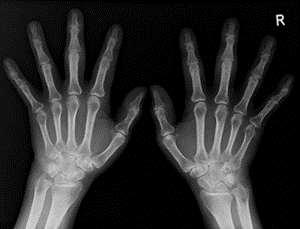

一般撮影

一般撮影検査(単純X線撮影・レントゲン)は、X線を使って胸部、腹部、骨などの静止画像を得る、最も基本的な放射線検査です。短時間で痛みはなく、外来や救急、健診など幅広い場面で行われます。使用するX線の量は極々微量で、人体に影響があらわれる量ではありません。ただし、妊娠中またはその可能性がある場合は、事前にお知らせください。